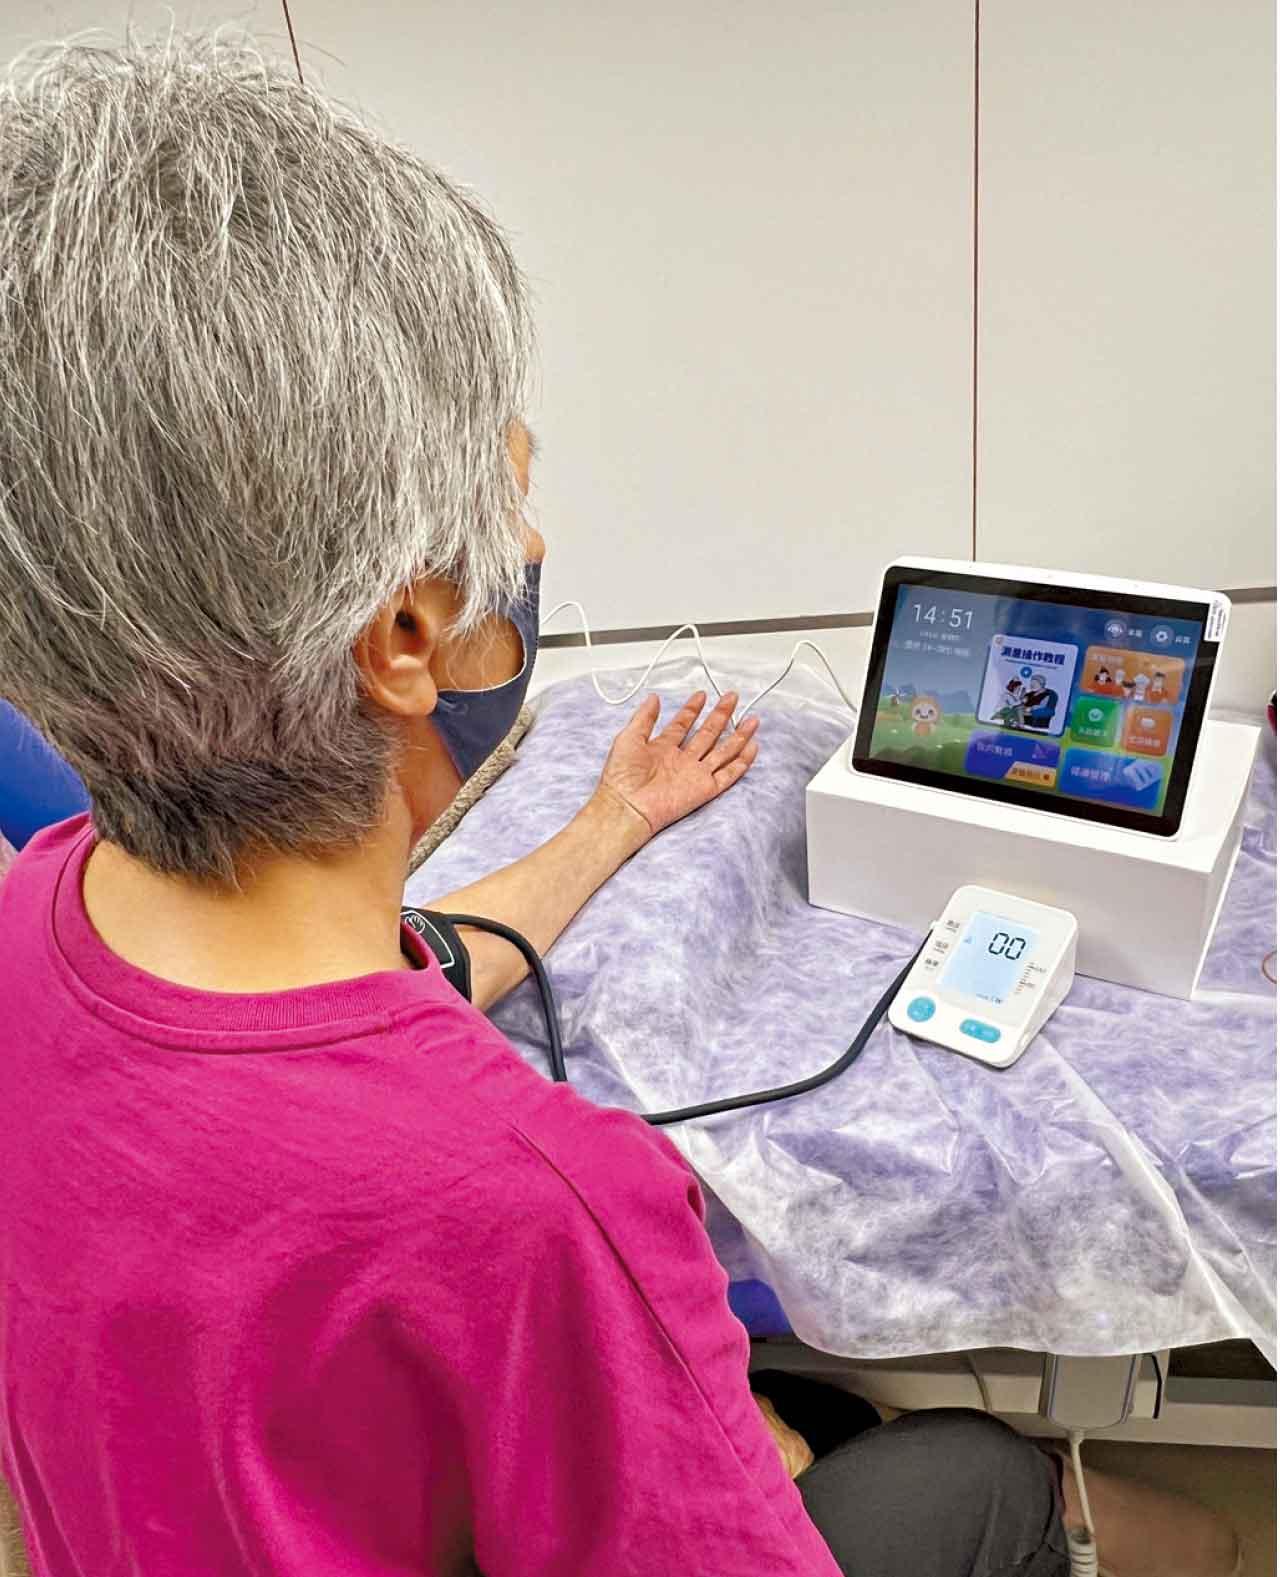

推出「智能健康監測及遙距持續護理服務」,體現無牆醫院概念。

為響應醫衞局對《基層醫療健康藍圖》所提出的建議,及早識別「三高」的慢性疾病病人以介入治療,播道醫院成功獲創新及科技基金下科技券計劃資助,開展了「智能健康監測及遙距持續護理服務」的試點項目。Canice指計劃的主要目標是在社區內有效篩查和監測病人。現階段院方會為病人提供具雲端數據傳送功能的血壓計,病人在家量度的血壓數據會安全準確傳送到醫院的監察系統,實踐無牆醫院的概念。此外,為提升客戶體驗,醫院亦推出「播道醫院手機流動應用程式」,方便用戶搜尋醫生和專業人員、預約服務、查詢最新身體檢查及其他推廣優惠。「我們的電子顧問會引導用戶搜索符合性別、需求和不同信用卡優惠的體檢計劃;亦可透過聊天機械人查詢醫院服務。」她表示會持續優化流動應用程式,未來病人將可查閱個人醫療紀錄,讓市民獲得更方便和全面的求診體驗。